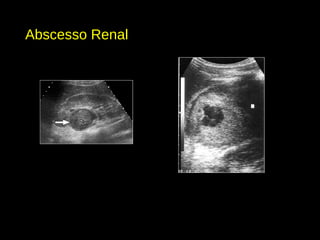

Abscesso Renal

• Coalescimento de microabscessos.

• Lesões hipoecogênica, de limites imprecisos, que atenuam parcialmente o feixe

sonoro.

• Evolução: maior determinação de seus contornos e liquefação central, com

conteúdo espesso, ecogênico, debris e septações, podendo gás nível líquido-

líquido.

• Cápsula fibrosa – indica processo crônico.

• Doppler: ausência de fluxo central e pobre mapeamento periférico.